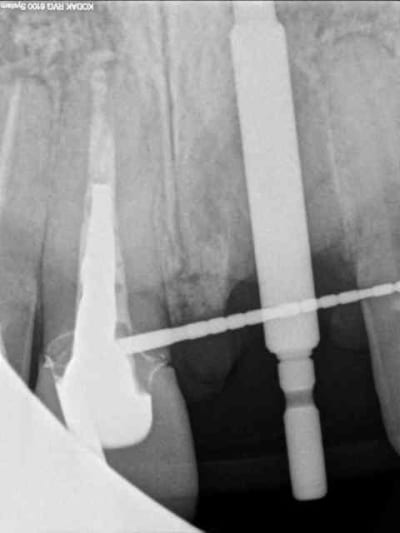

voici encore un autre cas avec du PX encore tout chaud de ce matin...

homme 35 ans veut faire recoller sa couronne 21.

le tenon est tordu, je refais une provisoire mais à la radio je lui dis que j'ai un doute quant à la survie de la dent parce qu'il y a une image pas très nette en mesial de la racine.

je l'envoi faire quelques coupes tomo (vivement que j'ai cone beam! )

le resultat est édifiant et sans appel; la racine est à extraire!

1 radio départ

1 radio départ

2-3-4 cas initiale avec provisoire

9 radio post op